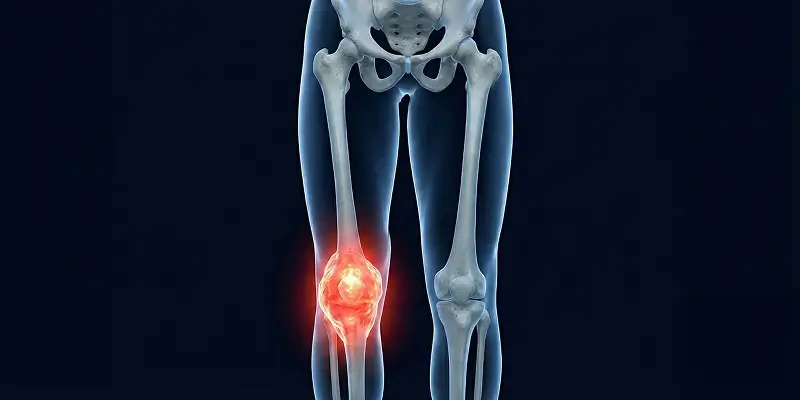

Gece artan kemik ağrısı, geçmeyen şişlikler ve sebepsiz kırıklar kemik tümörü habercisi olabilir. Erken tanı hayat kurtarır, belirtileri öğrenin.